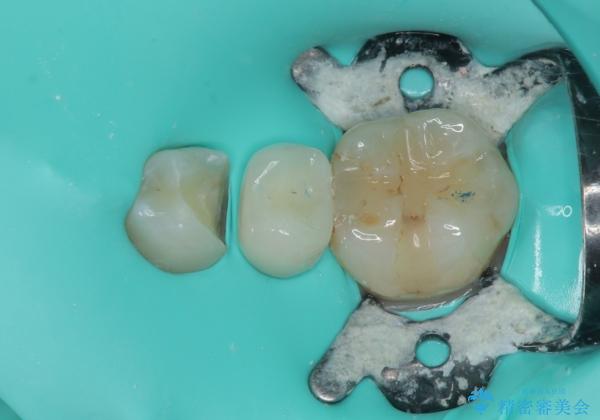

拡大鏡視野下で被せもの、虫歯の除去を行い、オールセラミッククラウン、セラミックインレーに適した形に整えました。

歯と歯茎の間に圧排糸と言われる糸を入れてシリコーン印象材にて精密な型どりをしました。

セラミックインレーの装着時には、唾液の侵入を防ぐために、ラバーダム防湿を行いました。